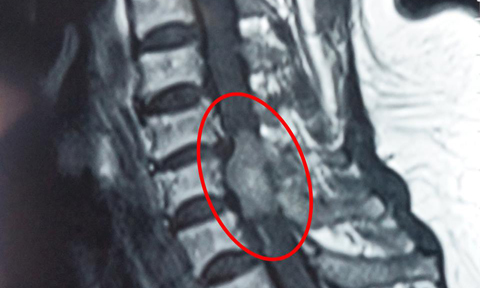

Kết quả kiểm tra cho thấy, bệnh nhân có khối u rất lớn chèn ép vào tủy sống, phá hủy xương các đốt sống từ tháng 9 đến tháng 12.

Xác định đây là ca bệnh phức tạp, BV đã hội chẩn nhiều chuyên khoa để có phương án xử lý tối ưu, xác định đây là ca mổ cấp cứu, ưu tiên số 1 là cắt bỏ khối u để giải phóng chèn ép tủy sống, lấy mẫu sinh thiết.

Ekip quyết định mổ từ lưng, giải phóng chèn ép, bóc tách lấy sạch khối u kèm theo lấy một phần thân các đốt sống từ T9 đến T12 bị mủn nát. Phần còn lại của đốt sống còn khá nhiều nên không cần phải thay thân đốt sống. Ca mổ kéo dài hơn 5 giờ, khối u lấy ra có kích thước lên tới 12x5cm.